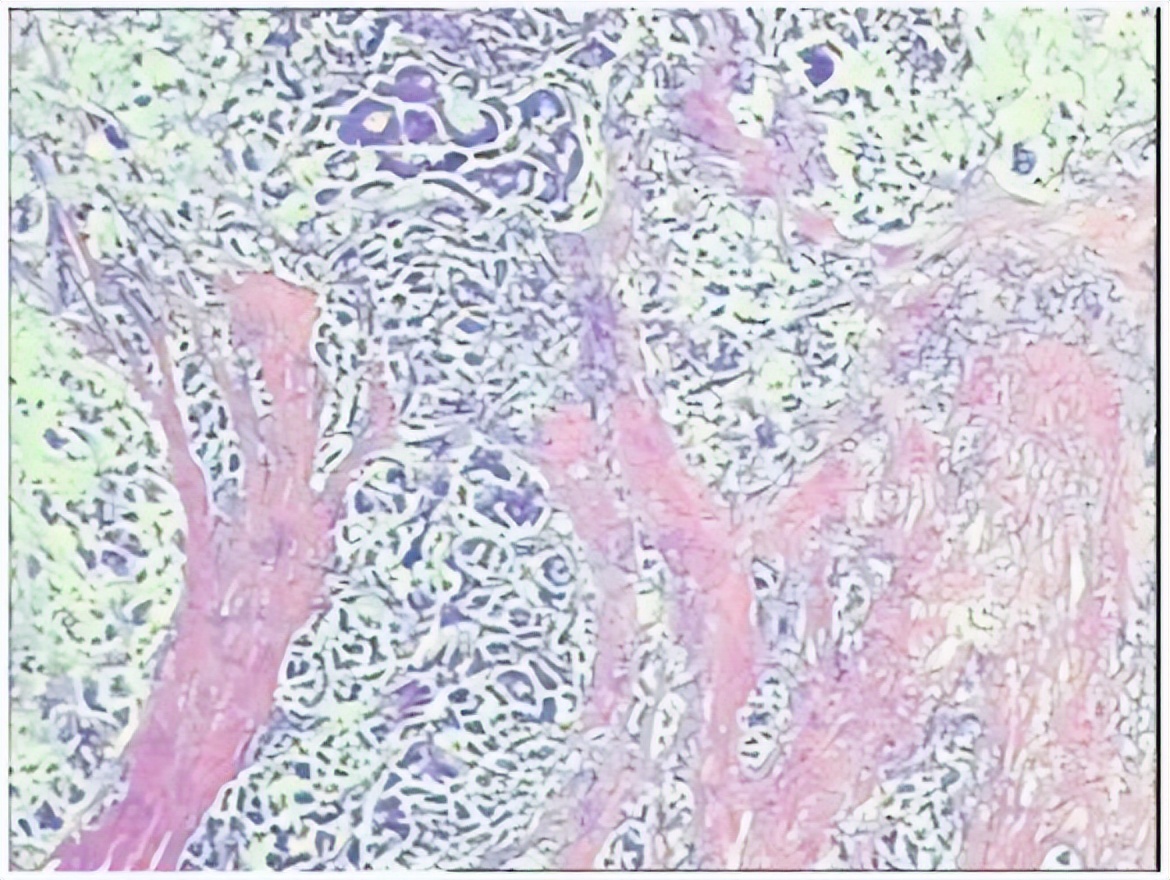

术后病理:直肠下段中分化腺癌,侵犯外膜下脂肪组织,肿瘤出芽分级(高级别,Bd3),侵犯神经侵犯,未见确切脉管内癌栓;两侧手术切缘、环周切缘及标记切缘内均未查见癌累及,肠周淋巴结内未查见转移癌(0/17)。pTNM分期:pT3N0Mx。免疫组化结果:CK(+),MSH2(+),MSH6(+),MLH1(+),PMS2(+),MDR-1(3+),HER2(3+),P53(3+),Ki-67阳性率约70%。